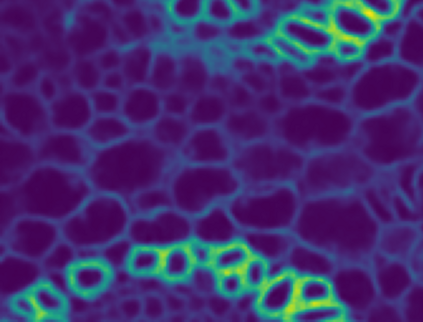

Microscopy images often suffer from high levels of noise, which can hinder further analysis and interpretation. Content-aware image restoration (CARE) methods have been proposed to address this issue, but they often require large amounts of training data and suffer from over-fitting. To overcome these challenges, we propose a novel framework for few-shot microscopy image denoising. Our approach combines a generative adversarial network (GAN) trained via contrastive learning (CL) with two structure preserving loss terms (Structural Similarity Index and Total Variation loss) to further improve the quality of the denoised images using little data. We demonstrate the effectiveness of our method on three well-known microscopy imaging datasets, and show that we can drastically reduce the amount of training data while retaining the quality of the denoising, thus alleviating the burden of acquiring paired data and enabling few-shot learning. The proposed framework can be easily extended to other image restoration tasks and has the potential to significantly advance the field of microscopy image analysis.